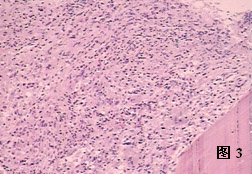

1) 早期全血細胞增生伴輕度骨髓纖維化期骨髓細胞呈程度不一的增生。紅、粒、巨核細胞系均增生,以巨核細胞最明顯。脂肪空泡消

骨髓纖維化失,網狀纖維增多,但尚不影響骨髓的正常結構。造血細胞占70%以上,骨髓基質以可溶性膠原蛋白增加為主。

2) 中期骨髓萎縮與纖維化期纖維組織增生突出,占骨髓的40%~60%,造血細胞占30%,巨核細胞仍增生。骨小梁增多,增粗,與骨髓相鄰部位有新骨形成。各個散在造血區域被由網狀纖維、膠原纖維、漿細胞和基質細胞形成的平行束狀或螺鏇狀物質分隔。

3) 晚期骨髓纖維化和骨質硬化期 MF終末期。以骨質的骨小梁增生為主,占骨髓的30%~40%。纖維及骨質硬化組織均顯著增生,髓腔狹窄,除巨核細胞仍可見外,其他系造血細胞顯著減少。此期骨髓基質成分中聚合蛋白為主,主要表現纖維連線蛋白,外連線蛋白和TENASCIN分布增加。

(二)骨髓塗片及活檢 骨髓穿刺約有1/3的病例呈現\乾抽\現象。骨髓塗片有核細胞增生低下,也可表現為增生性骨髓象。骨髓活檢找到大量網狀纖維組織,為診斷本病依據。根據骨髓中保留的造血組織和纖維組織增生的程度不同,骨髓病理改變可分為三期:①早期全血細胞增生伴輕度纖維組織增生;②中期骨髓萎縮和纖維化;③晚期骨髓纖維化和骨質硬化。

1、早期全血細胞增生伴輕度骨髓纖維化期:骨髓細胞呈程度不一的增生。紅、粒、巨核細胞系等均增生,以巨核細胞最明顯。脂肪空泡消失,網狀纖維增多,但尚不影響骨髓的正常結構。造血細胞占70%以上。骨髓基質以可溶性膠原蛋白增加為主。

2、中期骨髓萎縮與纖維化期:纖維組織增生突出,占骨髓的40%-60%,造血細胞占30%,巨核細胞仍增生。骨小梁增多、增粗,與骨髓相鄰部位有新骨形成。各個散在造血區域被網狀纖維、膠原纖維、漿細胞和基質細胞形成的平行束狀或螺鏇狀物質分隔。

骨髓穿刺約有1/3的患者會呈現乾抽現象;其中骨髓塗片有核細胞增生低下,也可以表現為增生性骨髓象;而骨髓活檢找到大量網狀纖維組織,也就是診斷繼

發性骨髓纖維化的依據;有關專家會根據骨髓中保留的造血組織和纖維組織增生的程度不同,將骨髓病理改變可分為三期:早期全血細胞增生伴輕度纖維組織增生;

中期骨髓萎縮和纖維化;晚期骨髓纖維化和骨質硬化。